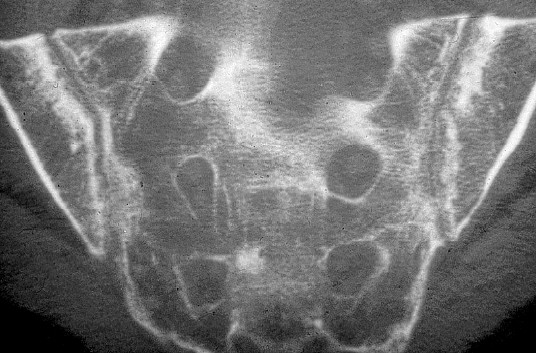

Fig. 1.6. Apport du scanner.

Sacro-iliite caractérisée par des érosions et des lésions d’ostéocondensation irrégulières des deux berges donnant l’impression d’un « pseudo-élargissement ».